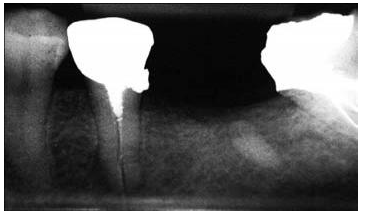

圖2:上頜第一前磨牙的根尖片,過長的平行壁樁修復(fù),根尖部的牙膠量少于理想的5mm的根尖封閉

對于牙體解剖、牙根結(jié)構(gòu)、形態(tài)及其變異的良好理解,同時(shí)使用恰當(dāng)?shù)念A(yù)備方向,能夠幫助牙醫(yī)在樁道預(yù)備過程中避免出現(xiàn)過多的切削牙體組織和牙根穿孔。預(yù)備樁道時(shí),器械的方向必須與根管的方向相平行(圖 5)。